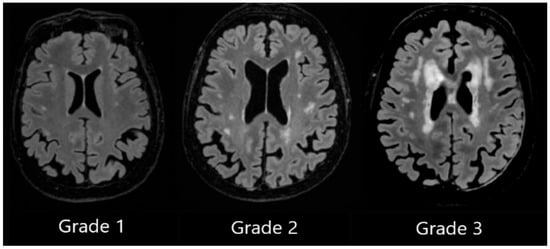

WMHs were quantified and delineated using Icometrix software (icobrain tbi report for MRI, version 5.12.0; Leuven, Belgium). The software identifies and evaluates WMHs by total volume and further categorises the lesions based on their anatomical regions (subcortical, periventricular, brainstem, and cerebellum), displaying volume values for each region. The software evaluates the volume of the whole brain, cortical grey matter, and the hippocampus. Moreover, Icometrix software compares these values to age- and sex-normative references from population data; however, in this study, we focused on WMHs (see Figure 3) [29].

Figure 3. Example of automated lesion delineation in axial, sagittal, and coronal planes. Yellow colour—periventricular white matter hyperintensities; blue colour—subcortical white matter hyperintensities.